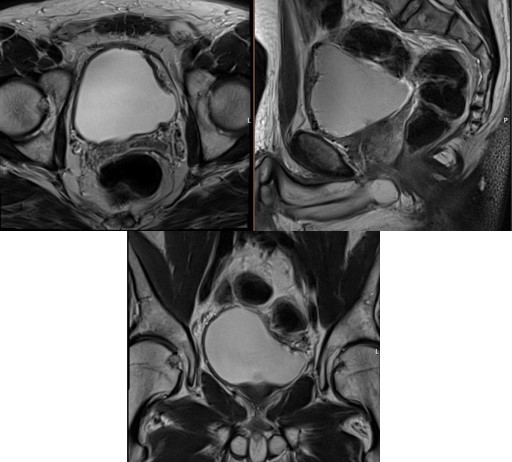

A fifty-nine-year-old male with no significant past medical history was admitted through accident and emergency to the referring hospital with acute clot retention. Initial conservative management with manual bladder washouts and continuous bladder irrigation, via three-way catheter, was unsuccessful, with ongoing transfusion dependent haematuria. An urgent CT urogram showed a solid 8 cm bladder mass and extensive intravesical clots (Figure 1).

Figure 1: (A) coronal view of non-contrast CT-KUB with solid looking mass in the left bladder wall and bladder full of clots. (B) Axial view of non-contrast CT scan showing same bladder mass with bladder full of clots. (C) Axial view of delayed excretory phase CT urogram showing rim of contrast surrounding large bladder clot.